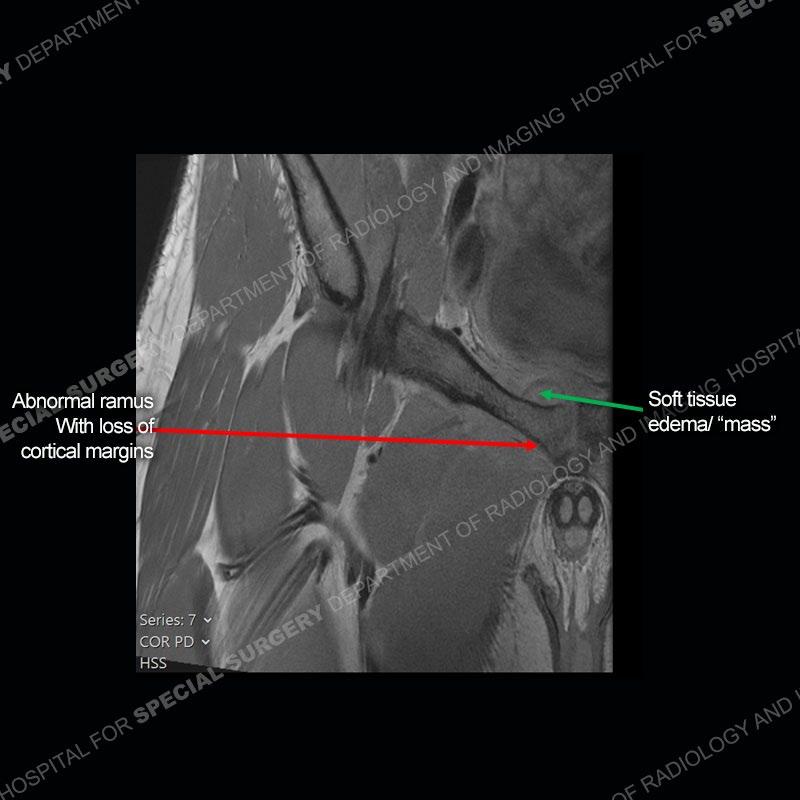

Radiographs did not demonstrate any clear abnormality. The MRI shows markedly abnormal signal of the right superior pubic ramus and abnormal signal/”mass” extending into the adjacent soft tissue. The inferior articular surface of the ramus showed what was thought to be bony destruction. CT examination shows a destructive process of the right superior pubic ramus.

Subsequent MRI in a very short time interval shows markedly increased abnormality of the ramus and increased edema and “mass” of the soft tissue. Post contrast imaging shows multiple, rim enhancing collections of the soft tissue and similar albeit less conspicuous enhancing collection of the ramus.